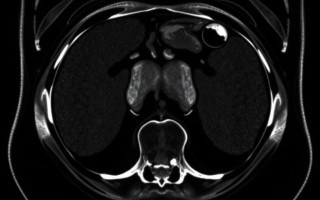

Для брюшной полости это особенно полезно: печень, желчный пузырь, поджелудочная железа, селезенка, почки и сосуды — все это можно рассмотреть в деталях. В отличие от УЗИ, МРТ меньше зависит от опыта оператора и от газов в кишечнике. И, что важно, МРТ не использует ионизирующее излучение, оно безопаснее по сравнению с компьютерной томографией, если речь о частых исследованиях.

Что может показать МРТ: конкретные примеры

Чтобы понять практическую пользу, полезно представить, какие состояния чаще всего выявляются с помощью МРТ брюшной полости. Ниже — таблица с примерами и пояснениями, что именно видит томография.

| Патология | Что показывает МРТ | Практическое значение |

|---|---|---|

| Опухоли печени | Локализация, характер васкуляризации, дифференциация доброкачественное/злокачественное | Планирование биопсии или операции |

| Хронический панкреатит | Изменение структуры поджелудочной, кисты, стенозы протоков | Выбор тактики лечения, оценка риска осложнений |

| Сосудистые аномалии | Степень поражения сосудов, тромбозы, портальная гипертензия | Определение необходимости интервенционной терапии |

| Метастазы | Мелкие и множественные очаги в паренхиме органов | Стадирование и выбор схемы лечения |